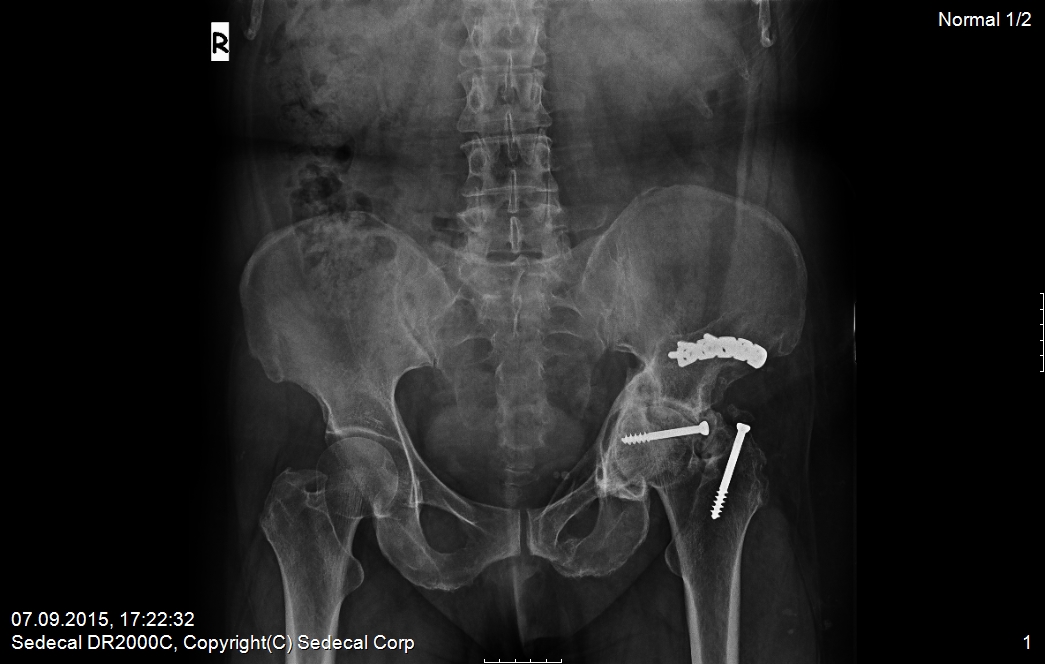

11 Şub Kalça kırığı sonrası protez tedavisi by admin in KALÇA CERRAHİSİ VAKA ÖRNEKLERİComments ameliyat sonrası kalça kırığı sonrası ameliyat geçirmiş hasta